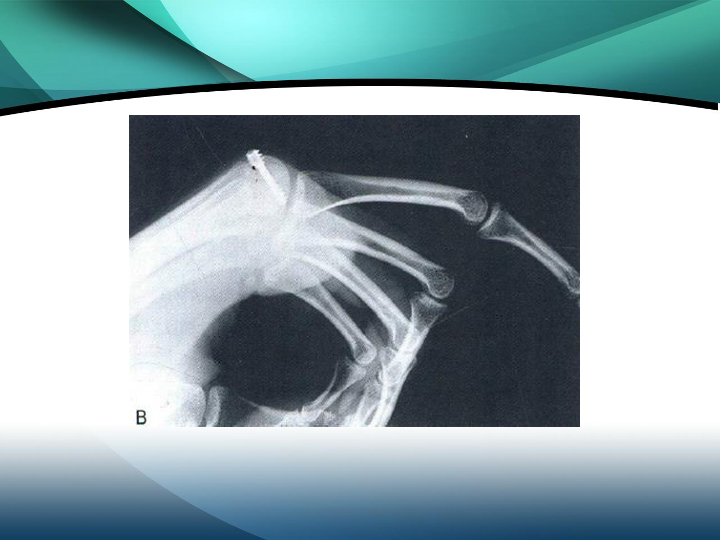

掌骨骨折